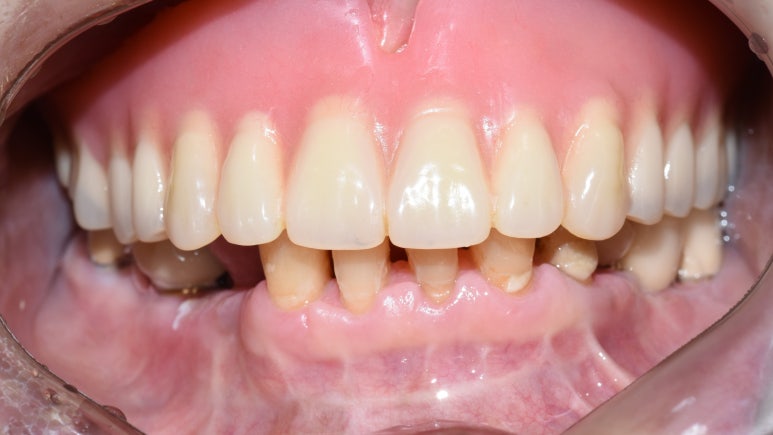

상악 전체 임플란트 후

- 상악 전체임플란트 및 하악 어금니 없는 부위 임플란트